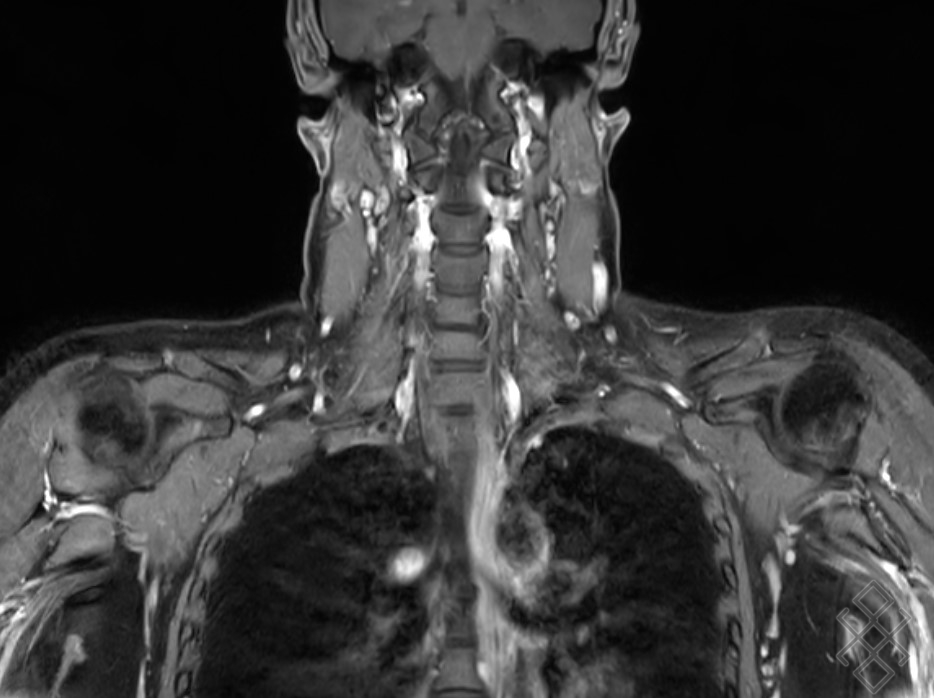

Image radiologique IRM normale du thorax

et de mediastin en coupe coronal pondere sur T1 FS

gadolinium |